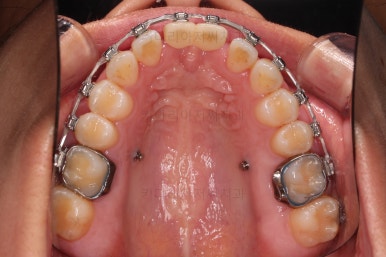

4. 마무리

앞니 임플란트의 색깔, 모양 등으로 몇 번의 수정 작업을 거친 뒤, 치료를 종료합니다.

잇몸뼈의 상태에 비해 매우 양호하게 임플란트가 완성되었고요.

개방교합, 2급 부정교합 등 모든 면에서 개선이 잘 되었습니다.